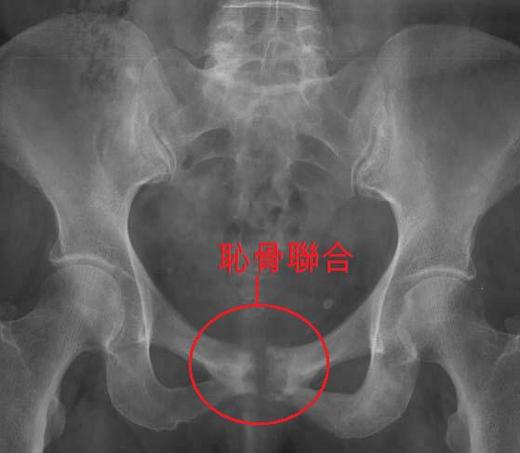

這種分裂分離的症狀多發生在產後,也就是生產後一個月左右,突然發作劇痛,無法上下床.利用 X 光攝影後發現,恥骨間的距離超過 "1公分"以上,就會發生劇痛,任何移動或牽動到下肢及骨盆的動作都會劇痛,行走更是困難。

正常女性的恥骨是在下腹部最底端處,是左右兩塊骨聯合的不動關節,大約只有 0.4 至0.5 公分的空隙。

然而少數女性反應過度或是" 放鬆素"過高,使正常分裂之距離超出達1.2公分,比原本正常的距離超出三倍之多.由於左右骨分裂後,造成腿部的伸展,及內外彎曲都成了問題.尤以移動最為劇痛.使不少才生產後媽咪,誤以為是骨折或是產傷併發症而到急診。

這位"倒著走"的準媽咪在產後第二天 X-光攝影發現,左右恥骨間距有1.2 公分之多,但產後第三天就不須 再" 倒著走" 了。